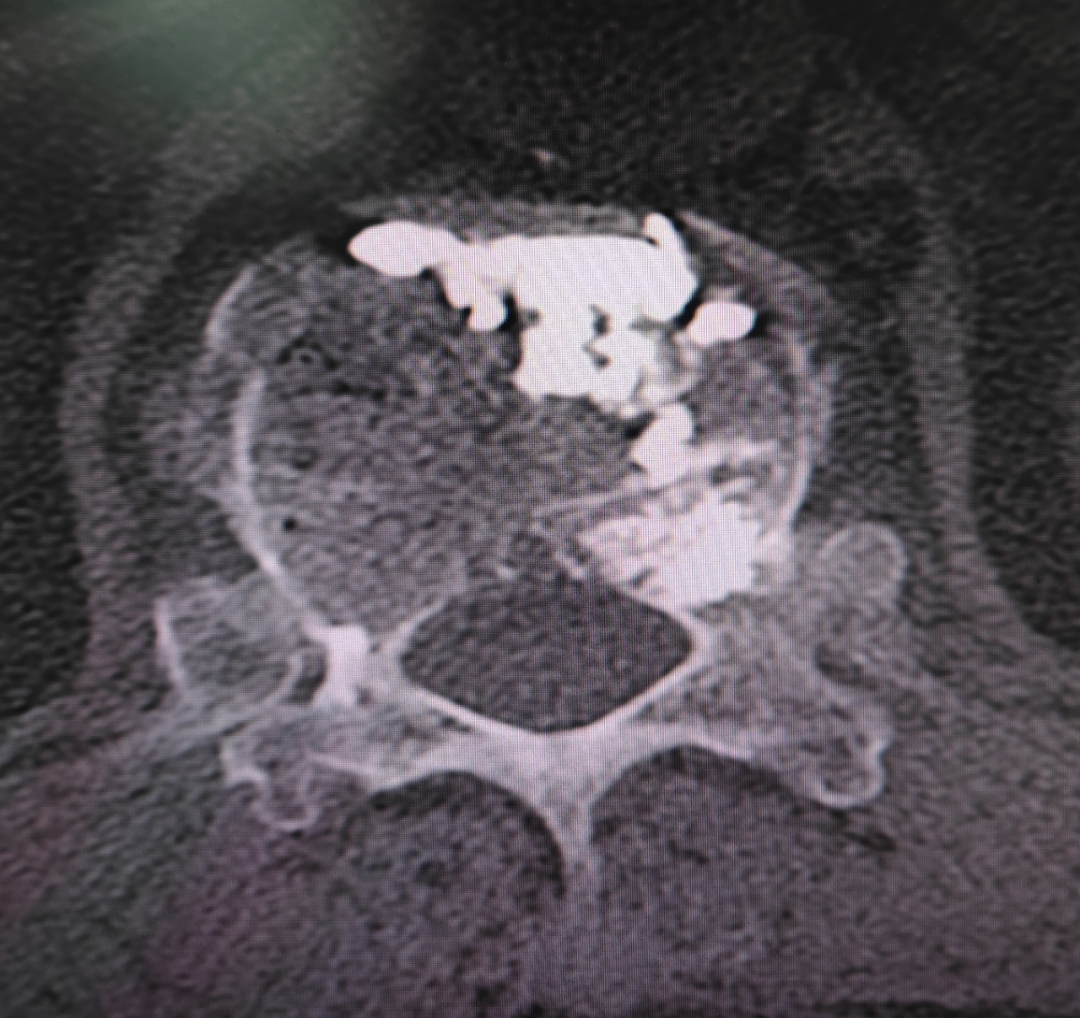

病例回顧 骨折部位 術(shù)中C臂協(xié)助定位 在C-臂監(jiān)視器透視下,分別定位胸12雙側(cè)椎弓根位置,標記穿刺點,僅以穿刺點為中心做3mm切開,在透視下注入骨水泥,再次透視見骨水泥位置良好。 骨水泥注入 術(shù)后影像學檢查 手術(shù)切口1cm左右 該手術(shù)經(jīng)皮透視下穿刺,手術(shù)切口小,創(chuàng)傷小,無需縫合,術(shù)后患者即感腰部疼痛明顯減輕,第二天可下床行走,已無腰痛不適,張大娘非常高興,自己再也不會受腰痛折磨整日與床為伴了。 我院脊柱骨科近年來,已成功開展多臺PVP手術(shù),為廣大老年患者減輕了病痛,減少了患者臥床時間,提高了生活質(zhì)量,是骨質(zhì)疏松性椎體骨折患者的福音。如果家里的老人突然出現(xiàn)了腰背疼痛,翻身下床困難,或者出現(xiàn)了腹部不適,排除腹部疾病(因為很多胸腰椎骨折患者在早期以腹痛腹脹為最主要癥狀),無論有沒有外傷史,建議帶老人及早就醫(yī),如果發(fā)現(xiàn)椎體損傷,積極治療,讓老人度過一個輕松愉快的晚年生活。 科普小講堂:經(jīng)皮椎體成形術(shù) 什么是骨質(zhì)疏松性椎體骨折? 骨質(zhì)疏松性椎體壓縮骨折,即在日常生活中患者并未遭受到明顯的外力而發(fā)生的骨折。這種骨折與創(chuàng)傷性的骨折不同,是由于自身骨質(zhì)疏松所導(dǎo)致的骨組織病變。骨質(zhì)疏松性骨折發(fā)生時,患者會感覺到背部明顯疼痛,翻身或起床等動作會讓疼痛更加明顯。 骨質(zhì)疏松性椎體壓縮骨折的危害有哪些? 一旦椎體發(fā)生骨質(zhì)疏松性椎體壓縮骨折,常常會導(dǎo)致患者出現(xiàn)腰背部持續(xù)性疼痛、季肋部放射痛、后凸畸形、呼吸功能受限及胃腸道癥狀等諸多癥狀,造成老年患者生活質(zhì)量下降。 什么是經(jīng)皮椎體成形術(shù)? (Percutaneousvertebroplasty,PVP)是一種新型的脊柱微創(chuàng)手術(shù),通過采用經(jīng)皮穿刺的方法,經(jīng)過椎弓根或是直接向椎體中注入骨水泥,使得椎體的強度和穩(wěn)定性得以提升,防止塌陷,從而達到緩解腰背疼痛,甚至部分恢復(fù)椎體高度的目的。 PVP手術(shù)優(yōu)點是什么? 1.恢復(fù)顯著:通常術(shù)后6個小時即能達到穩(wěn)定固定,患者可下床站立活動,大大縮短了患者臥床的時間。 2.疼痛減輕:術(shù)后患者會發(fā)現(xiàn)腰背部疼痛明顯減輕。 3.微創(chuàng):該治療方法僅需在皮膚上留2-3mm的穿刺針孔。 4.安全性:由于手術(shù)采用的是局部麻醉,因此即便是存在多種基礎(chǔ)病的患者也能夠耐受手術(shù),整個手術(shù)過程相對安全。 就診地址 酒泉市中醫(yī)醫(yī)院四樓脊柱骨科 咨詢電話 一樓門診部:0937-2669161 王醫(yī)生:13209409826 ??? 張醫(yī)生:18219971722